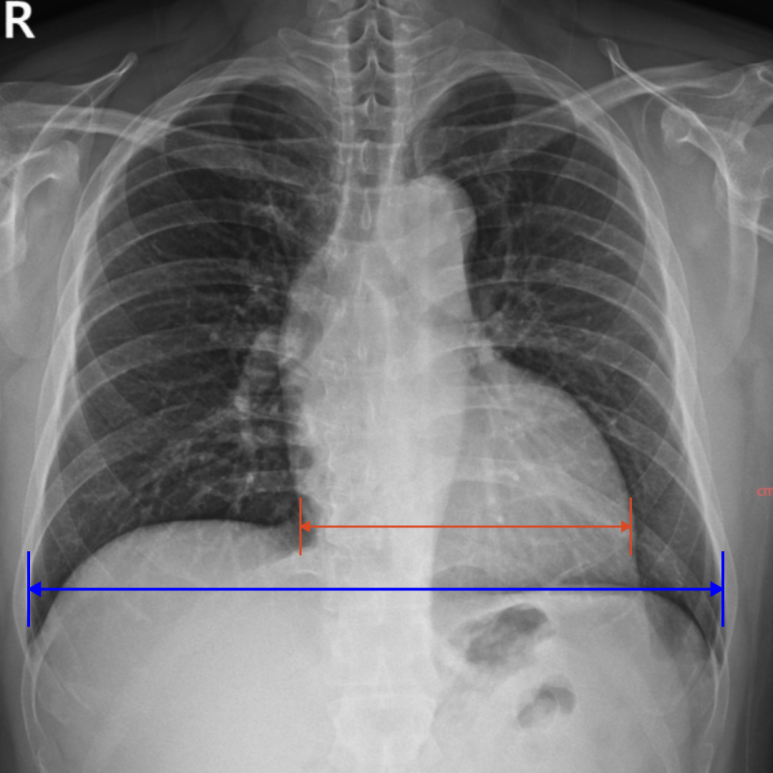

1. 흉부 X-ray

X‑ray에서는 폐 이상 없이 심장 크기 경계성 증가. 심전도에서 심비대 맟 심질환 의심 소견으로 심장초음파 추가 검사 결과 좌심실 기능 저하가 뚜렷하여 심부전에 합당, 고혈압 및 심부전 정도를 고려할 때 상급병원 입원 치료 연계.

• X‑ray: 경계성 심장비대 X‑ray: 경계성 심장비대